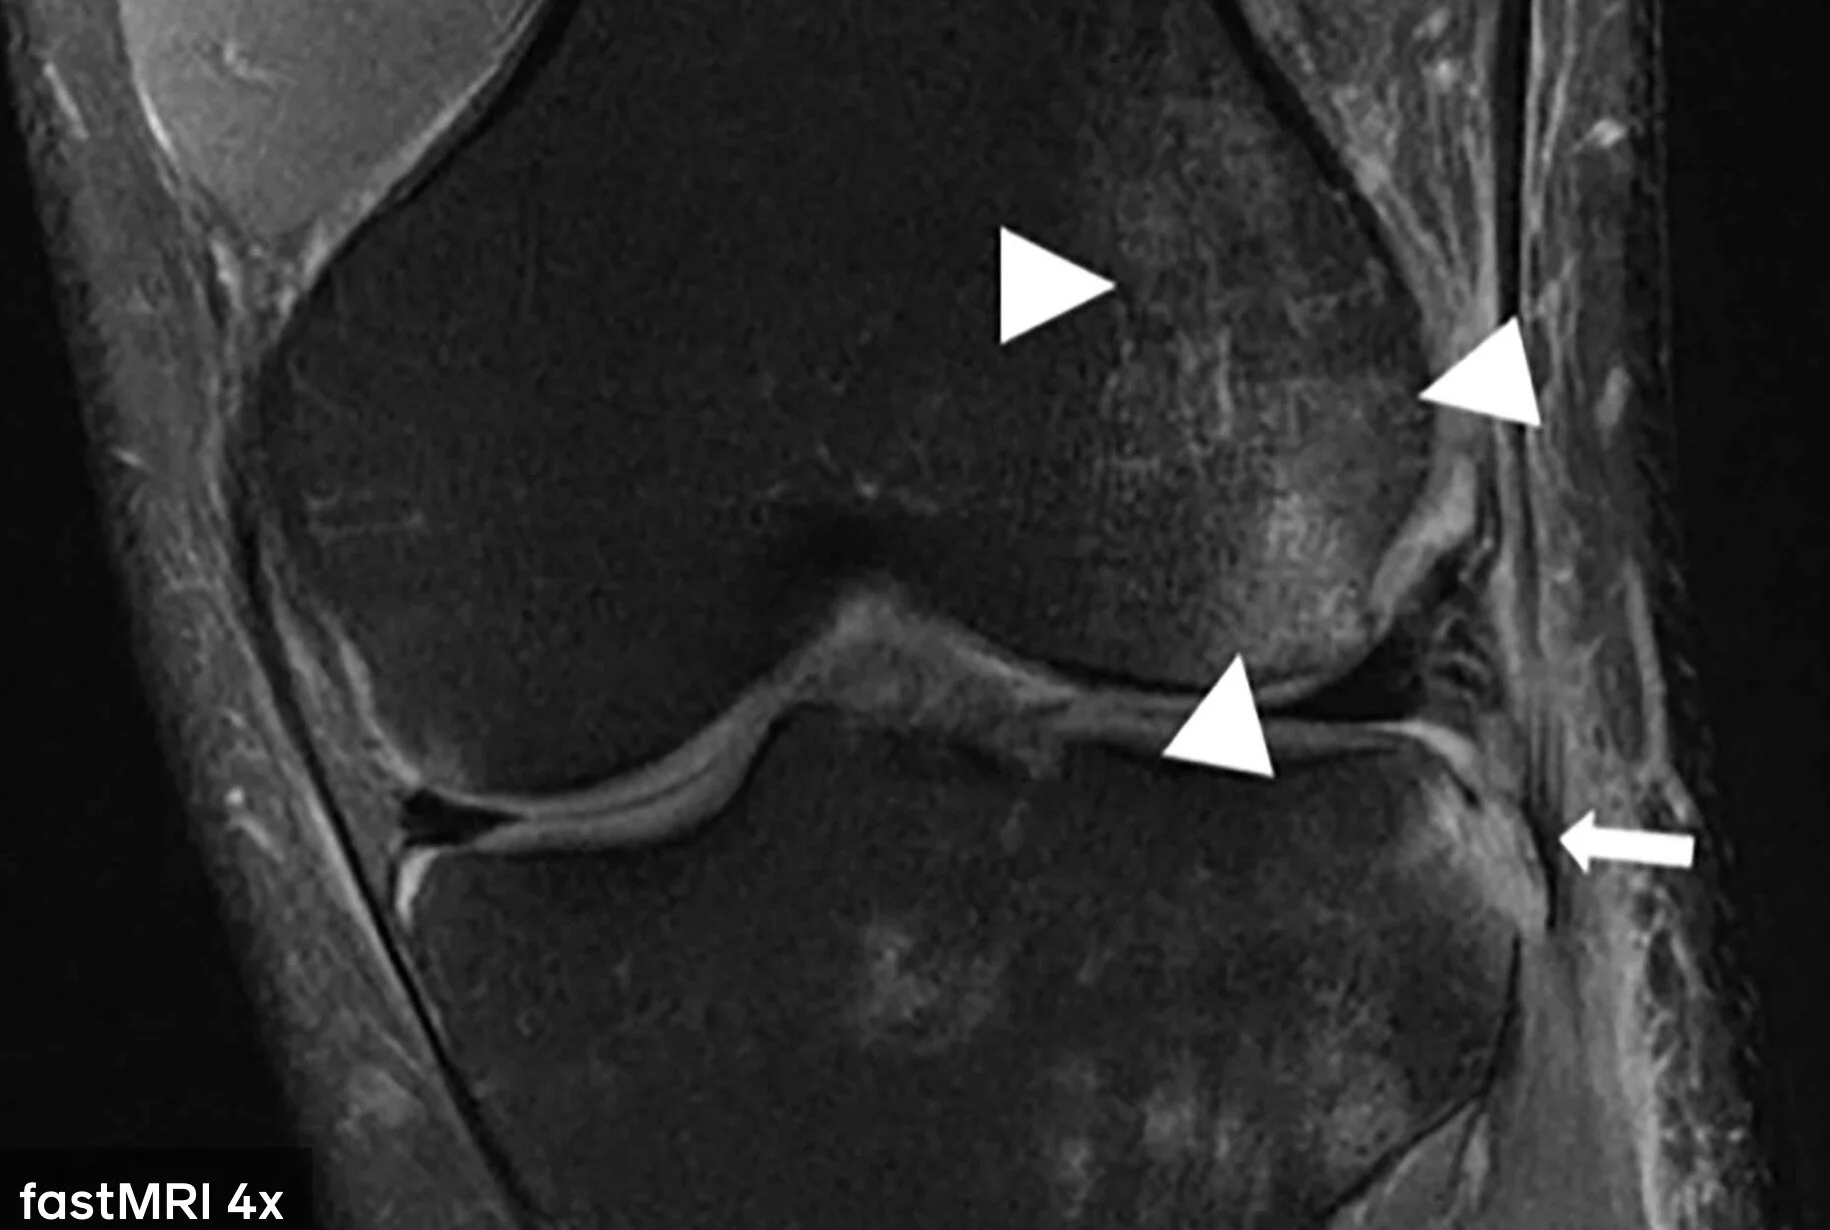

One way of minimizing these unpleasant experiences is by reducing the time spent in the tube, without compromising the thoroughness, quality & accuracy of the scans, because otherwise this would lead to wrong diagnosis. This is where the AI comes. fastMRI is a research project run by Facebook and NYU. The aim is to be able to reproduce accurate scan images with 4x less data using AI image reconstruction technology. By being able to leverage less data, patient has to spend less time. You can read more about how the ML Model works here.

MRI scan result generated by the AI model. Source: FB

4x less raw data used for AI MRI scan. Source: FB